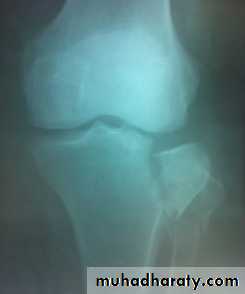

Tibial plateau fractures:Direct blow or fall from height may cause fracture of one tibial condyle or both.

Fracture lateral condyle is the commonest named as bumper fracture

caused by a force that abducts the tibia upon femur while the foot is fixed on ground.Patient usually is an adult, the knee joint is swollen, bruises, there is diffuse tenderness and doughy feel of haemarthrosis.

ligaments injuries must be excluded.

Imaging : X-ray

: anteroposterior, lateral & oblique views.

CT -Scan may used to detect amount of depression and comminuation.Tibial plateau fracture